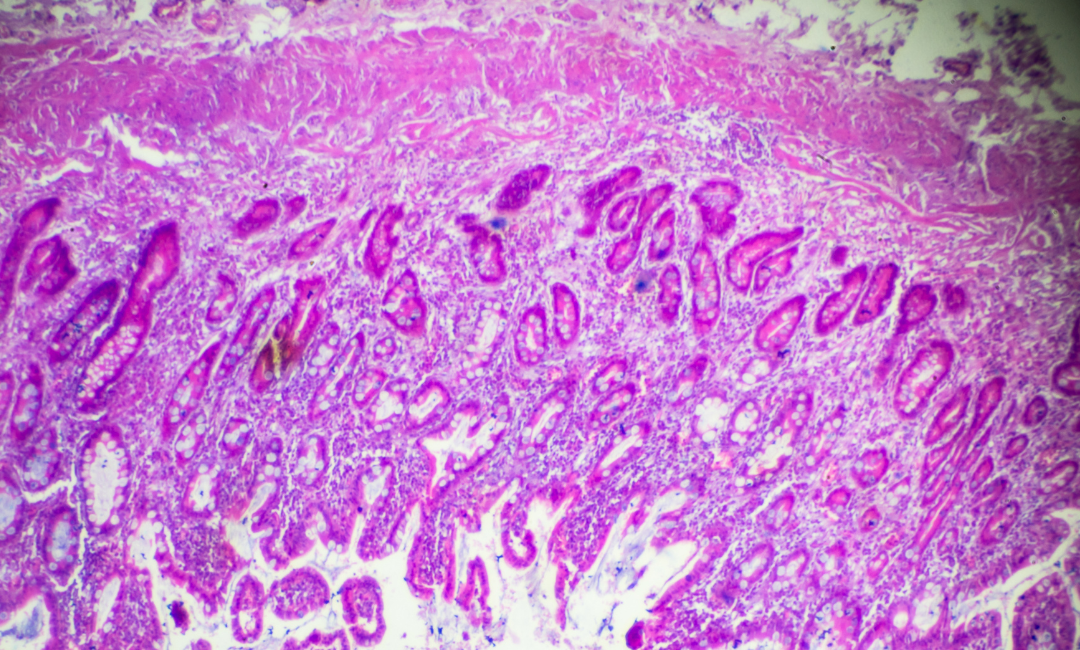

Os tumores cancerígenos podem ter diversas características e são nomeados de acordo com elas. Um exemplo é o adenocarcinoma, que tem origem nas células glandulares epiteliais, aquelas que produzem secreção.

A partir da biópsia e do exame imunohistoquímico, é possível conhecer as particularidades do tumor. Com essas informações, o médico oncologista consegue definir os tratamentos mais adequados.